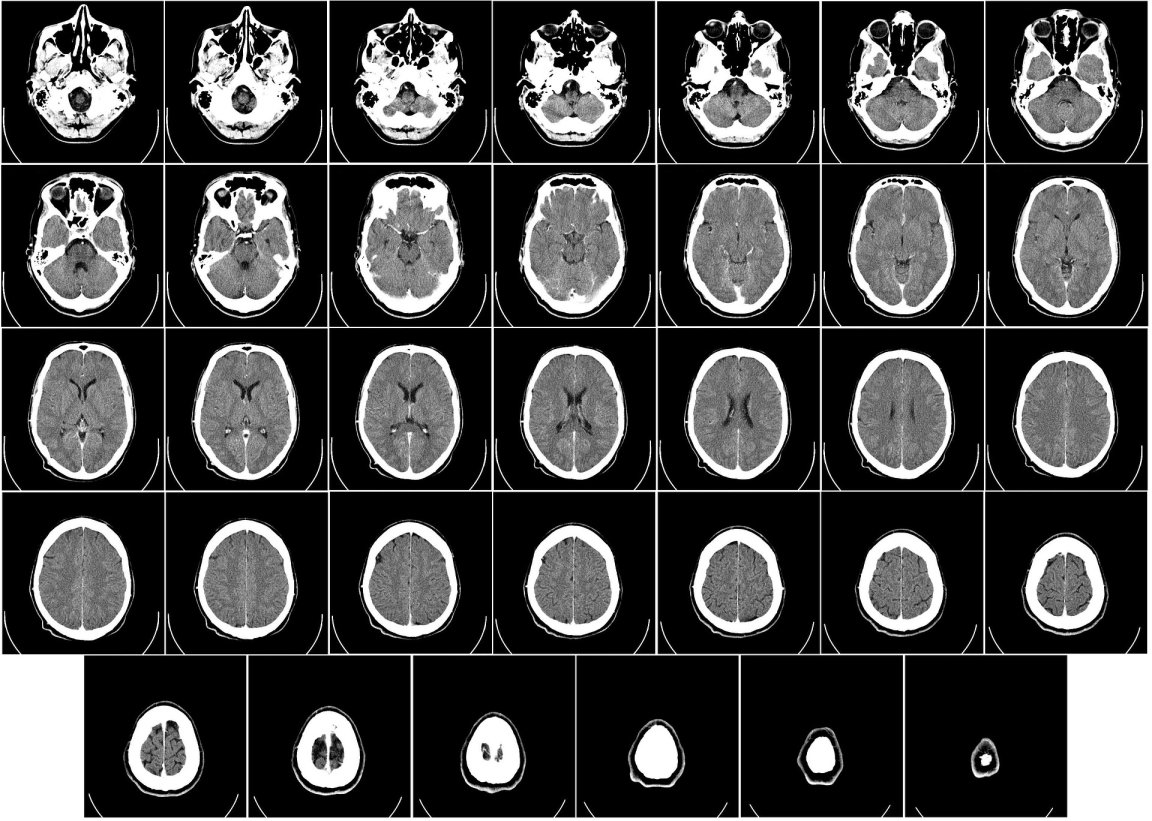

This procedure, otherwise known as thrombectomy, is carried out using a catheter inserted into the femoral artery, which is then threaded through the aorta. From there, it enters the cerebral arteries where it locates the blood clot responsible for the stroke.